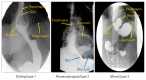

Methods: We assessed normal subjects (n = 20), patients with sliding type 1 hernia (n = 18), paraesophageal type 2 hernia (n = 19), and mixed type 3 hernia (n = 19). Hernia diagnosis was confirmed on the upper gastrointestinal series. The hiatal morphology was constructed from the CT scan images. The LES pressure and relaxation, percent peristalsis, bolus pressure, and hiatal squeeze pressure were assessed by HRM.

Results: The CT images revealed that the esophageal hiatus is formed by the right crus of the diaphragm in all normal subjects and 86% of hernia patients. The hiatus is elliptical in shape with a surface area of 1037 mm2 in normal subjects. The hiatal dimensions were larger in patients compared to normal subjects. The HRM revealed impaired LES relaxation and higher bolus pressure in patients with paraesophageal compared to the sliding hernia. The hiatal pinch on HRM was recognized in significantly higher number of patients with sliding as compared to paraesophageal hernia.